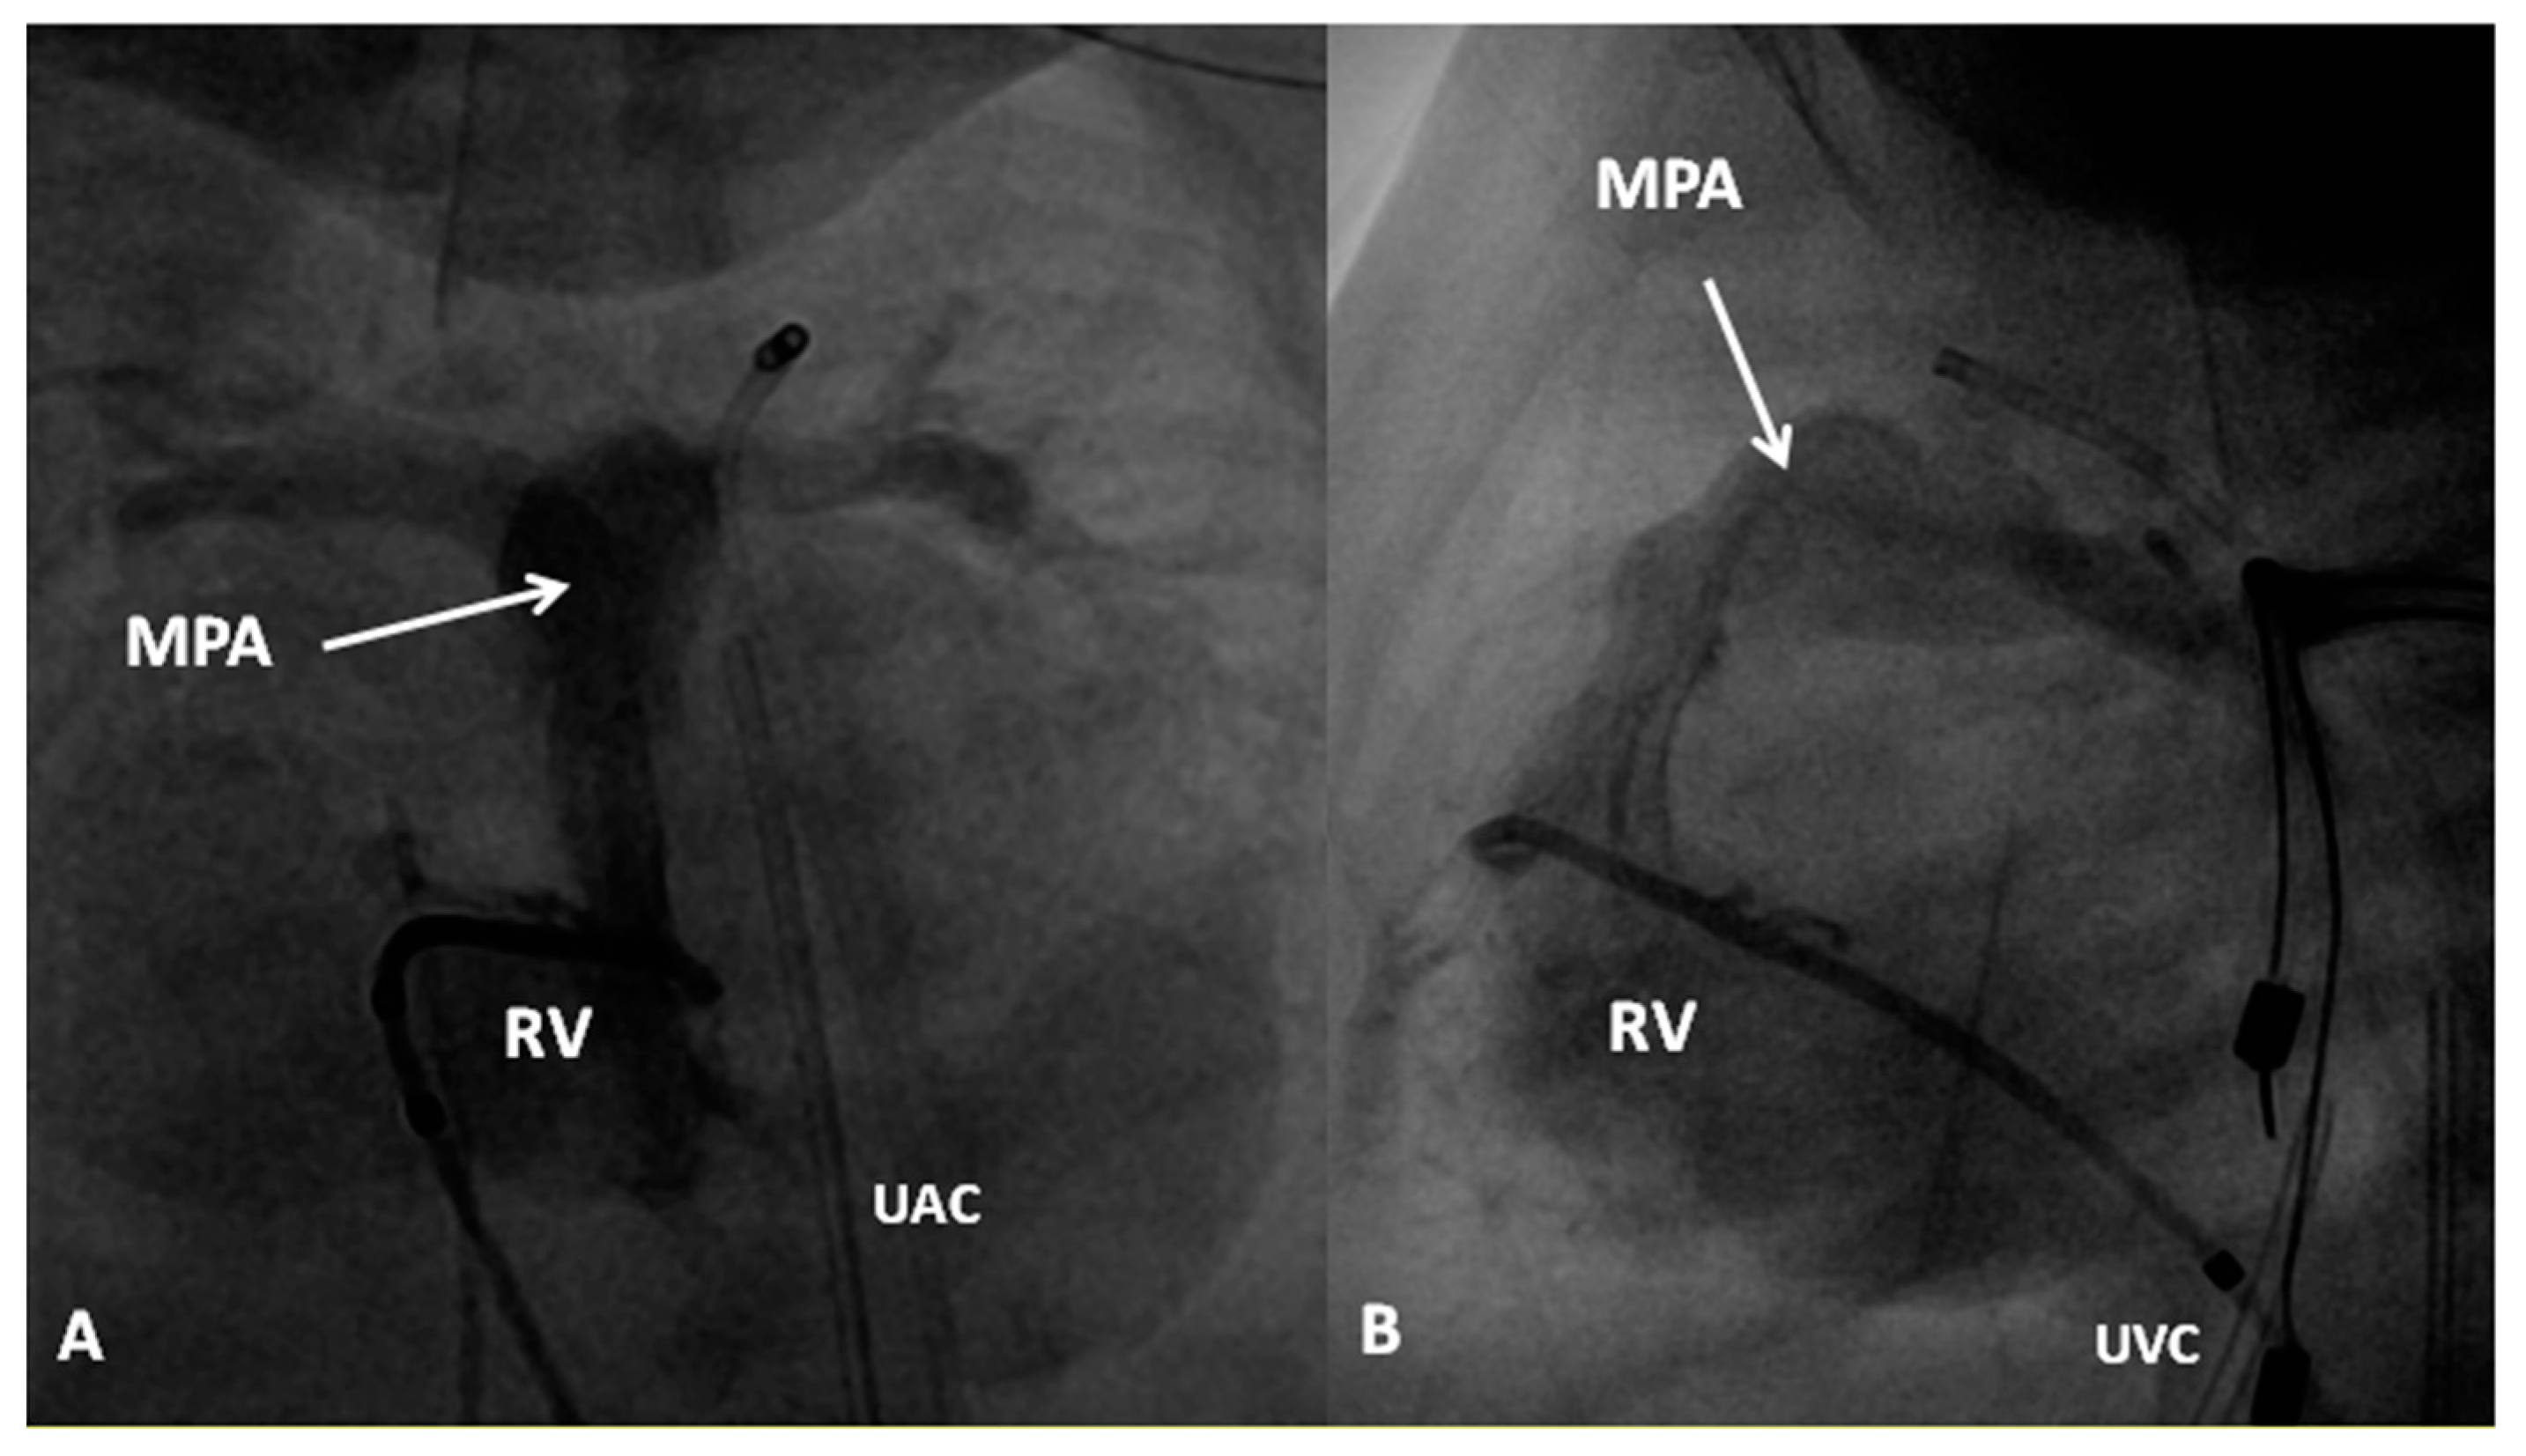

In premature babies two different palliative procedures were used as a bridge to total correction later. Balloon pulmonary valvuloplasty has been used in premature babies with TOF and significant arterial desaturaion as a bridge to total correction [17]. Similarly, deployment of a stent in RV outflow tract (Figure 3) may be used to promote growth of the pulmonary arteries and facilitate complete surgical correction at a later time [18].